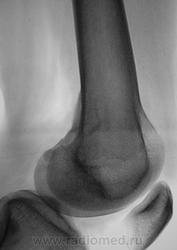

Энхондрома ? Но учитывая ячеистость, нельзя исключить гиганто-клеточную.

А, на "такое" не похоже?

Думаю, что похоже. Видится дефект в кортикальном слое.

И.Бондаренко wrote:

Так значит НОФ?